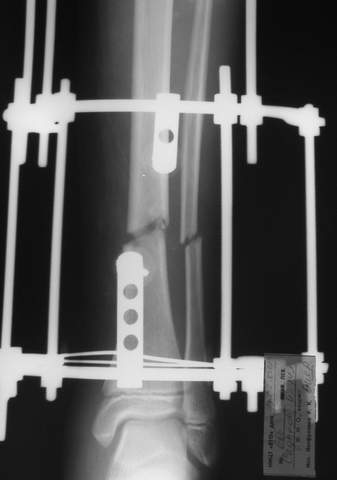

В аттачтах №№ 1 и 2 - примеры, когда 2 кольца не позволили послеоперационно

исправить смещение фрагментов большеберцовой (по ширине и вальгусное).

А казалось бы (#2) - поиграй на штангах и все влетит.

Оперировал не я

:-)

2